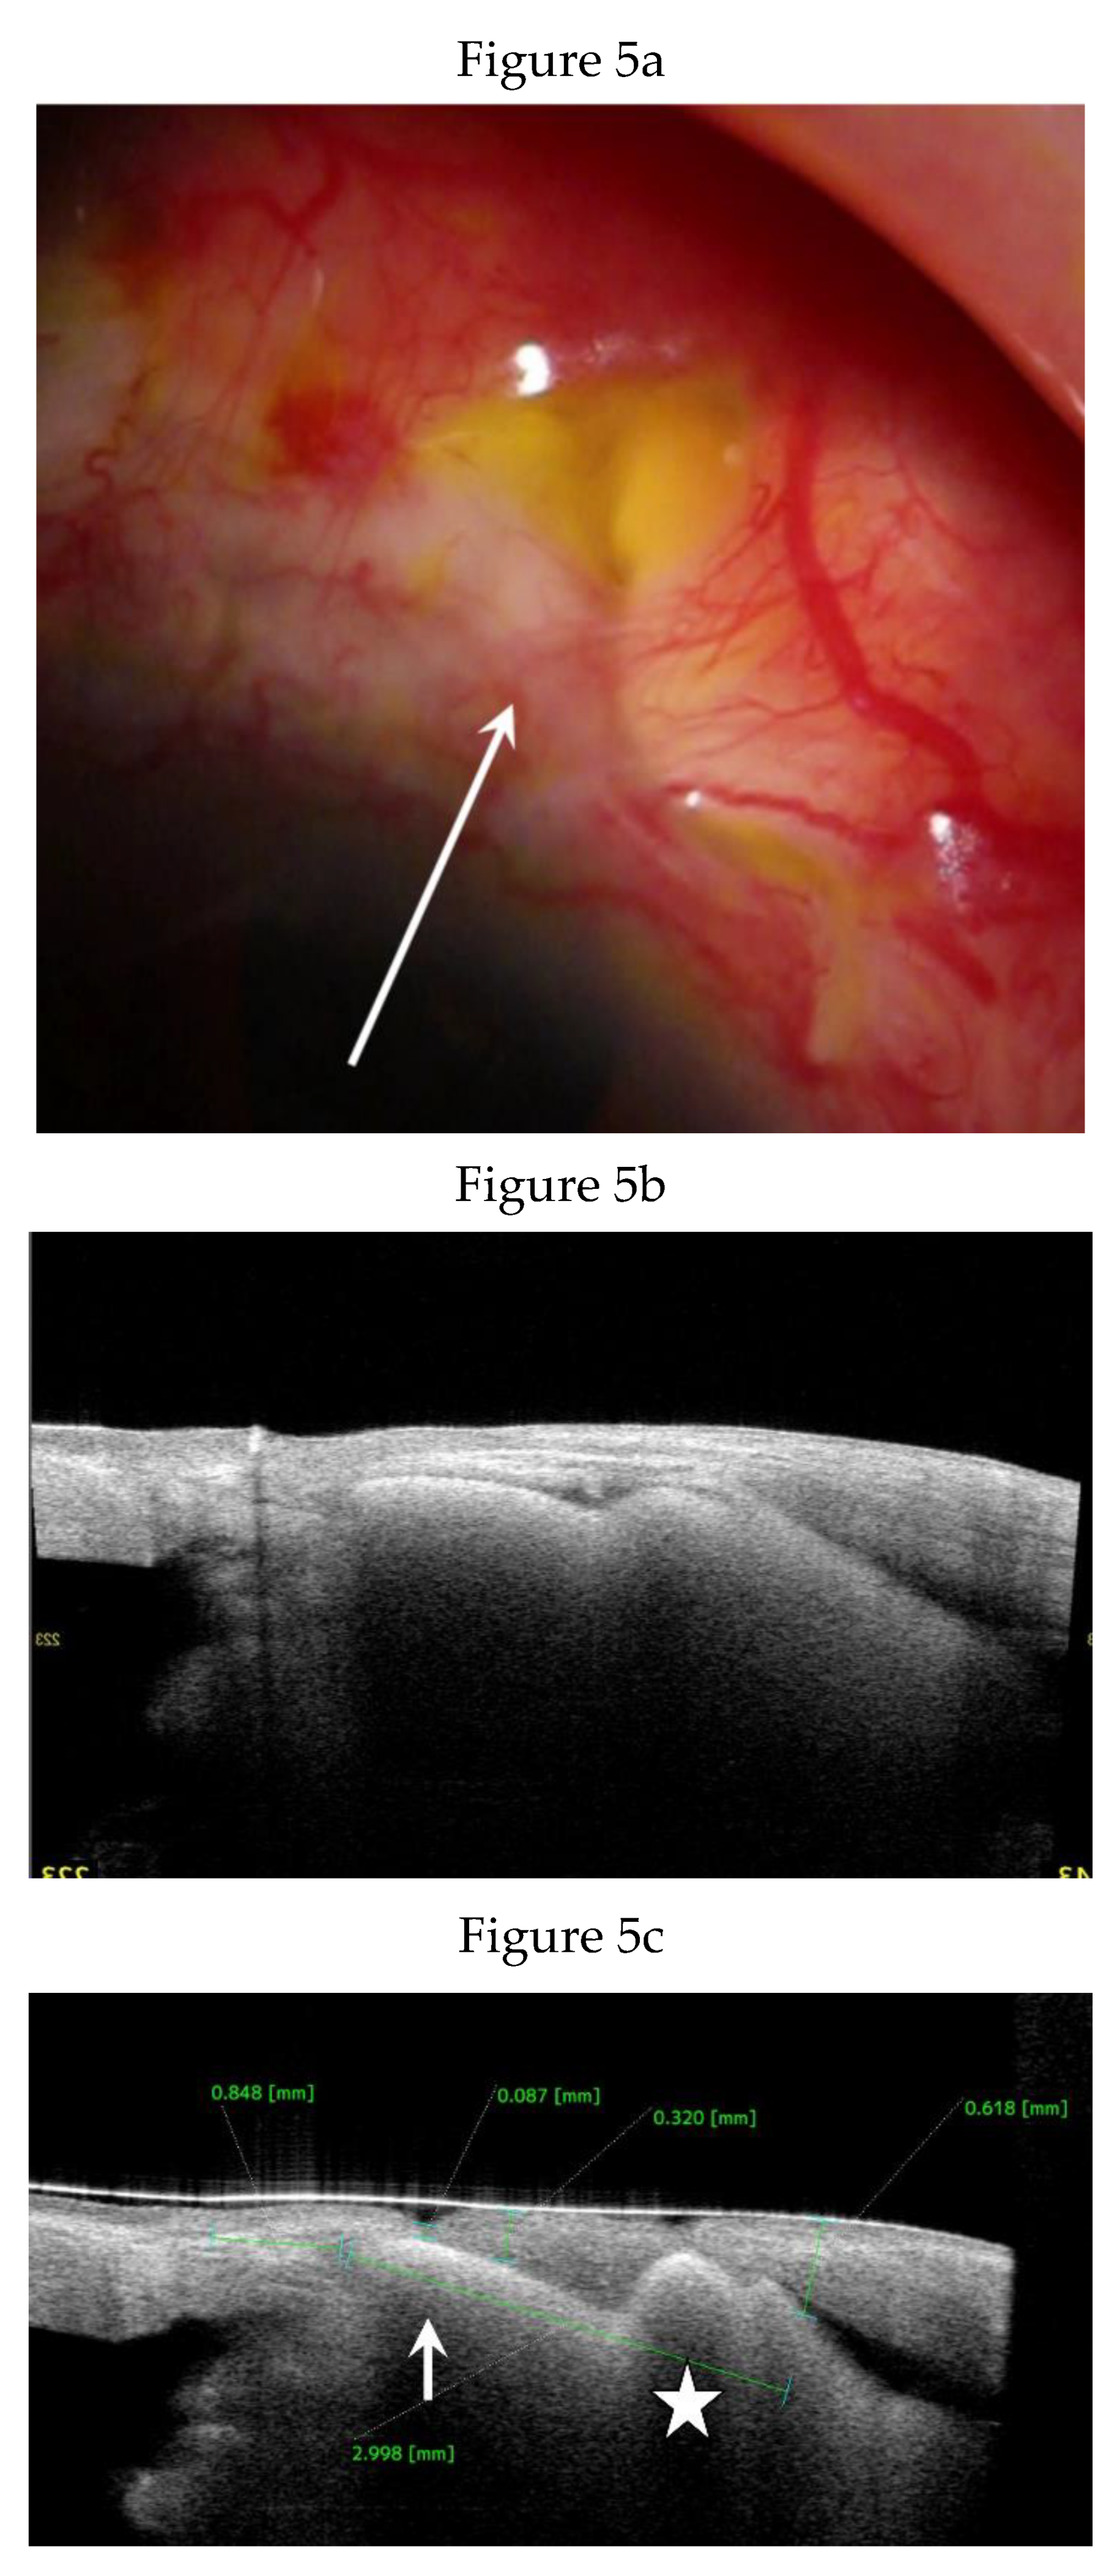

Clinical Course and Conjunctival Thickness in a Representative Case